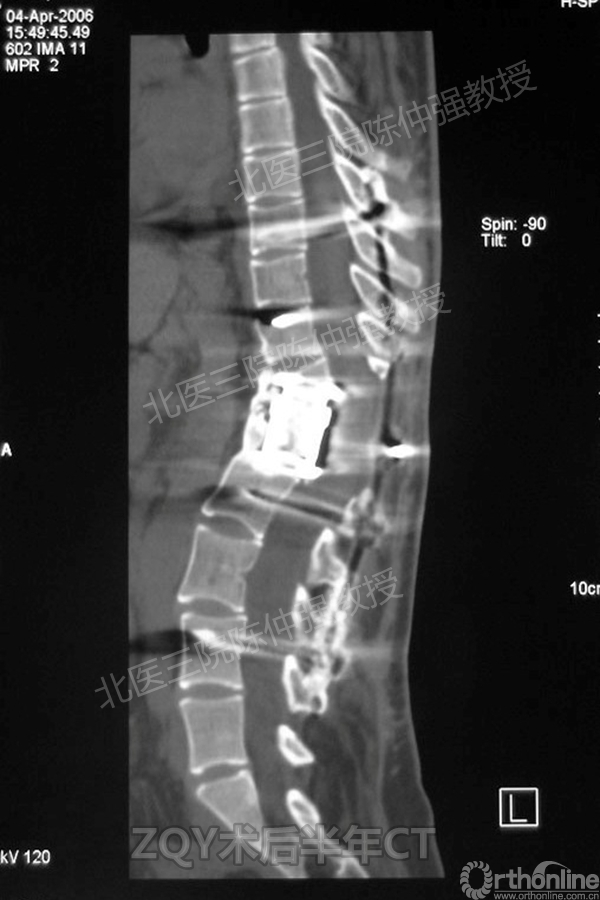

ZQY术后半年

患者女性17岁,胸腰椎陈旧结核性侧后凸畸形,局部呈“麻花状”扭转,无神经功能受损表现。2005年,陈仲强教授带领团队实施后路+侧前方联合入路脊柱节段切除、双轴旋转矫形术。术后患者外观显著改善,神经功能正常。术后随访证实患者截骨矫形节段骨性融合良好,矫形效果持续良好。